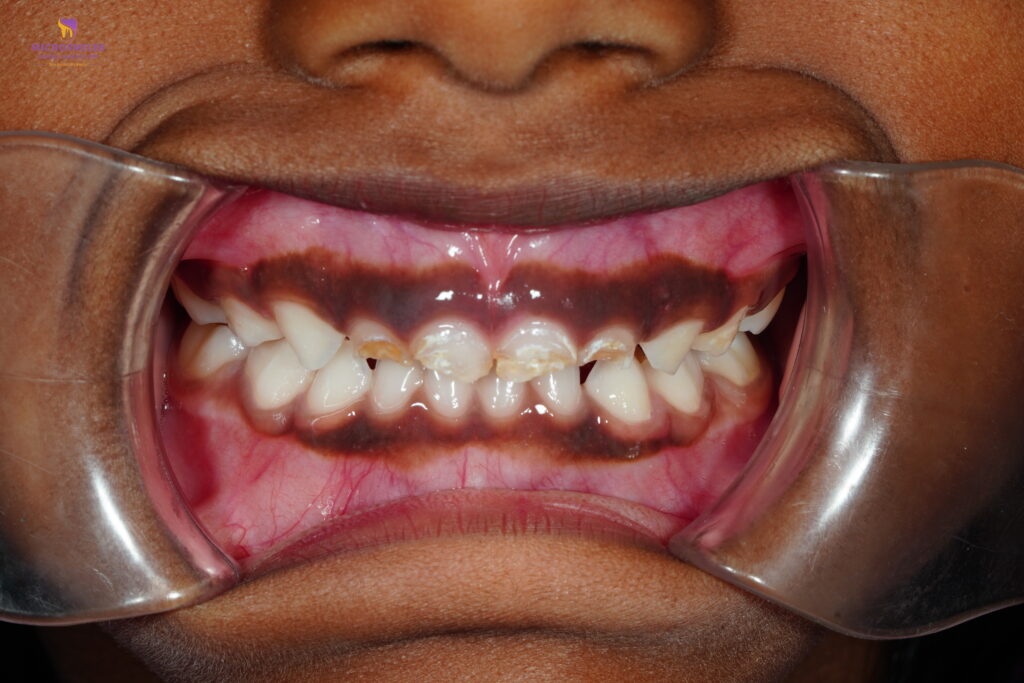

When your child has a severely decayed or infected baby tooth, removing it isn’t always the best option. At Microsmiles Dental Care, our pediatric specialists offer Pulp Therapy (Kid’s Root Canal)-a safe, effective way to save baby teeth, relieve pain, and maintain proper dental development.

Pulp therapy is often called a “baby tooth root canal.” It involves removing the infected or inflamed part of the nerve (pulp) while preserving the rest of the tooth. It’s typically followed by a protective crown-allowing your child to chew, speak, and smile pain-free.